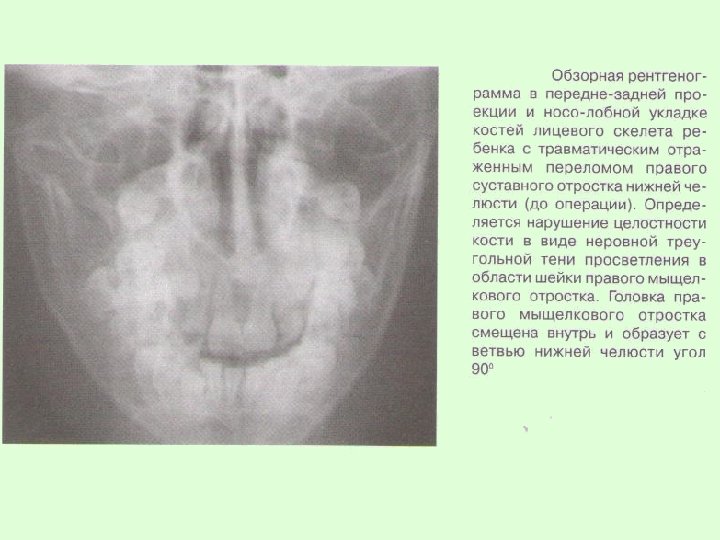

Заключительный диагноз перелома нижней челюсти ставят после проведения рентгенологического исследования в боковой укладке по Генишу или обзорной рентгенограммы нижней челюсти в прямой проекции, при переломе суставного отростка – ортопантомограммы или рентгенограммы сустава по Шуллеру или Парма.

На рентгенограммах обычно определяется нарушение целостности костной ткани, наличие линии перелома, смещение отломков челюсти. В сложных диагностических случаях переломов суставного отростка нижней челюсти у детей для постановки окончательного диагноза при отсутствии явных клинических и рентгенологических признаков используют метод спиральной компьютерной томографии с мультипланарной реконструкцией.